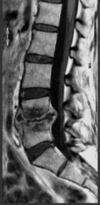

40-årig mand med ischias-symptomer. MR viser:

- a. Stor discusprolaps

- b. Absces

- c. Tumor

- d. Hæmatom

- e. Fremmedlegeme

*c. Tumor